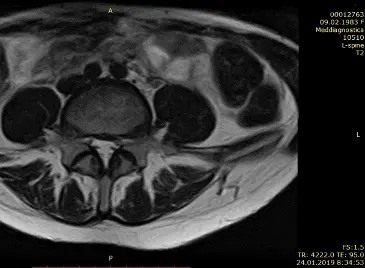

Бывают случаи, когда вправление грыжи можно провести за несколько сеансов. Иногда даже за один. Это возможно при протрузии диска и грыже небольшого размера. Если же грыжа большая и сопровождается болью в ноге, то для излечения понадобится курс лечения. Как это было с одной из наших многочисленных пациентов Ириной, результаты чего видны на МРТ, что ниже.